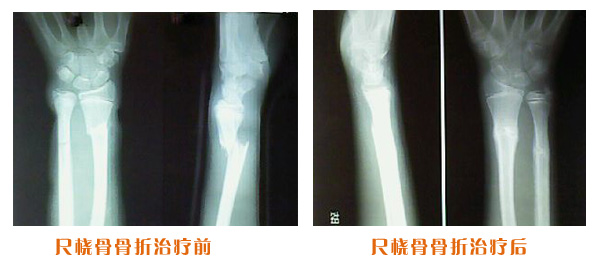

肥城市安駕莊梁氏骨科醫(yī)院是一所以梁氏手法正骨配合膏藥為特色的現(xiàn)代化專科醫(yī)院。

梁氏骨科術(shù)始創(chuàng)于清雍正年間,歷經(jīng)八代,至今已有三百年歷史。據(jù)1929年泰安縣志載“梁瑞圖先生,字增生,號(hào)蓮峰,安駕莊人,精岐黃并發(fā)明接骨,凡跌打車凡跌打車軋皮不破而碎骨者......【詳細(xì)】 |